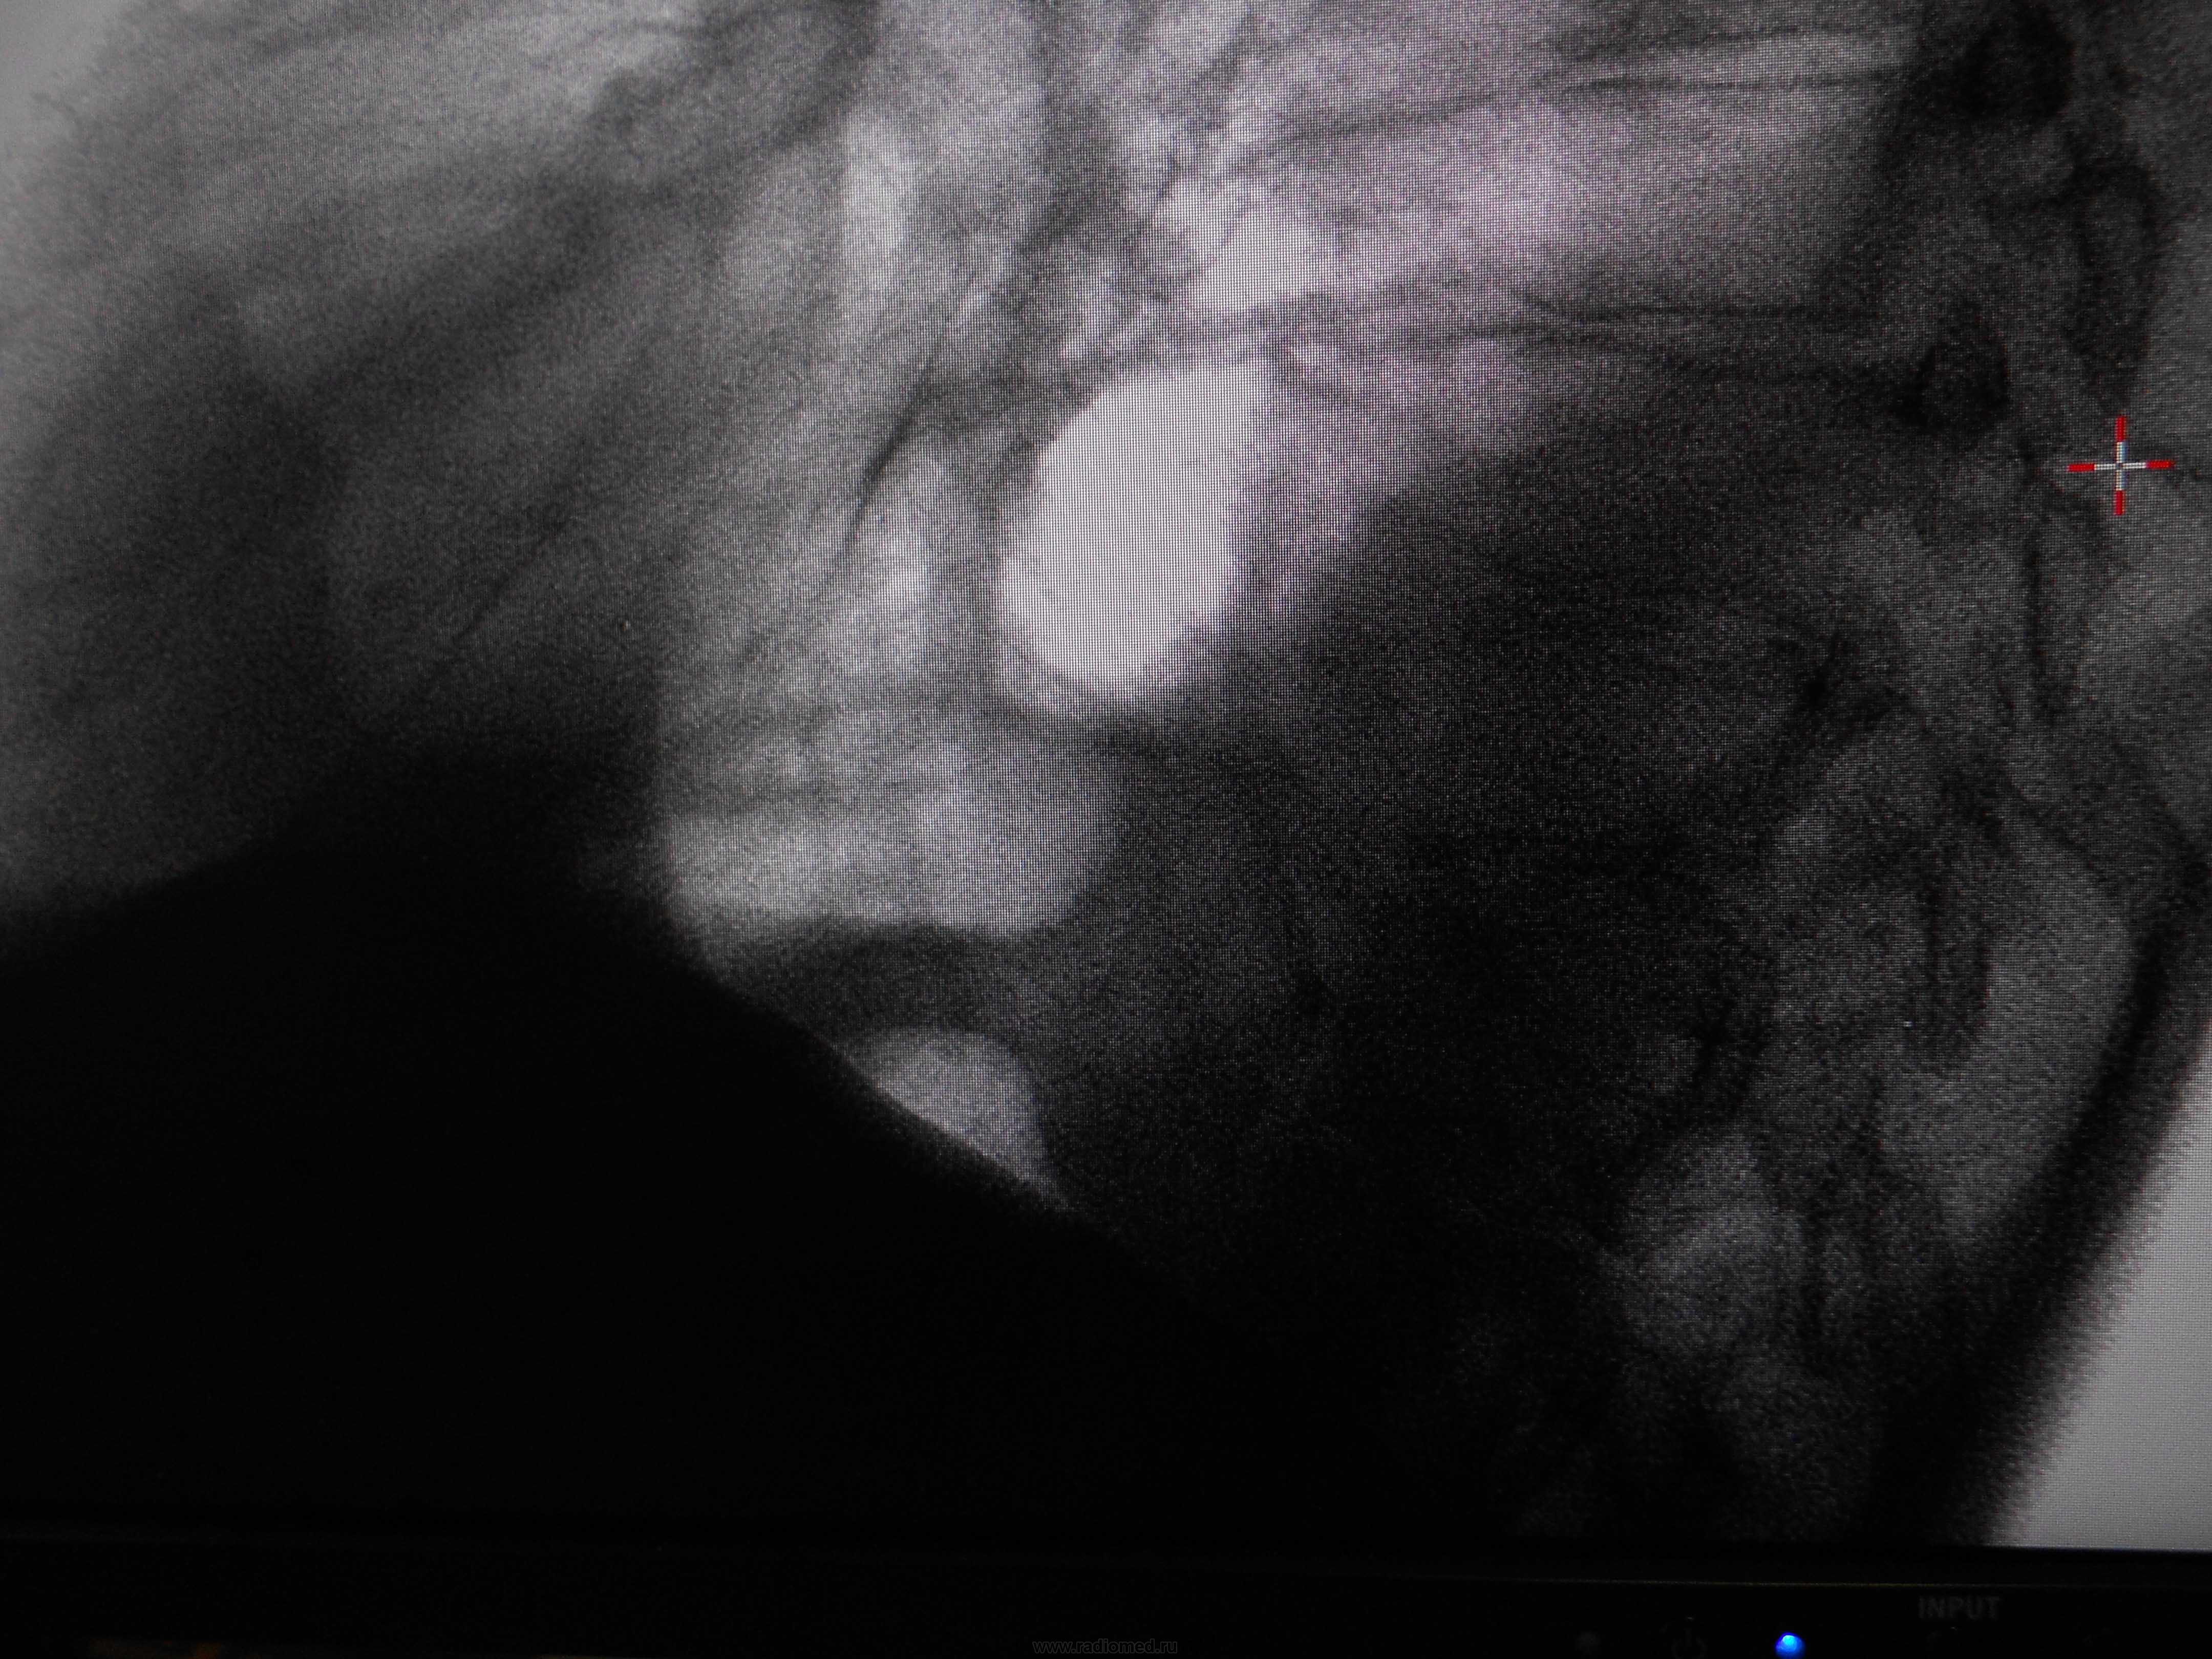

Пол пациента: Мужской пол Тип патологии: Другое Область исследования: Грудная клетка и верхние дыхательные пути Методы исследования: Rg Мужчина, 1983 года рождения, наркоман. Жалобы на затруднение дыхания, больше толком ничего не может сказать. Поставила просто показать, наверное это осумкованный плеврит, но очень уж форма причудливая) https://radiomed.ru/sites/default/files/styles/case_slider_image/public/user/16049/dscn0196-2.jpg?itok=VMOIZfz8 https://radiomed.ru/sites/default/files/styles/case_slider_image/public/user/16049/dscn0200-2.jpg?itok=jF8RVB_8 https://radiomed.ru/sites/default/files/styles/case_slider_image/public/user/16049/dscn0199-2.jpg?itok=d8mgQYPQ ID:25338 Пнд, 24/12/2012 - 21:04 #1 Катенёв Валенти... Не на сайте Был на сайте: 7 лет 2 недели назад Зарегистрирован: 22.03.2008 - 22:15 Публикации: 54876 Здравствуйте Мила! Задний паракостальный без сомнений! Пнд, 24/12/2012 - 23:58 #2 Наталия Васильевна Не на сайте Был на сайте: 5 лет 8 месяцев назад Зарегистрирован: 25.09.2011 - 09:02 Публикации: 754 Катенёв Валентин Львович wrote: Здравствуйте Мила! Задний паракостальный без сомнений! Согласна, вопрос как давно? Если процесс "свеженький"-может, пардон, шарахнуть в эмпиему в любой момент. Втр, 25/12/2012 - 01:11 #3 И.Бондаренко Не на сайте Был на сайте: 2 дня 13 часов назад Зарегистрирован: 13.09.2011 - 22:55 Публикации: 9206 Наталия Васильевна wrote: Катенёв Валентин Львович wrote: Здравствуйте Мила! Задний паракостальный без сомнений! Согласна, вопрос как давно? Если процесс "свеженький"-может, пардон, шарахнуть в эмпиему в любой момент. Пусть хирурги "шарахнут" пункцией. Тогда точно будете знать. Втр, 25/12/2012 - 03:06 #4 Mila85 Не на сайте Был на сайте: 3 года 1 месяц назад Зарегистрирован: 15.03.2012 - 16:59 Публикации: 1790 Катенёв Валентин Львович wrote: Здравствуйте Мила! Задний паракостальный без сомнений! Здравствуйте, мы на работе тоже так единогласно подумали. Давность неизвестна, пациент где-то частно наблюдается со своей зависимостью, туда и потопал

Задний паракостальный без сомнений!

Согласна, вопрос как давно? Если процесс "свеженький"-может, пардон, шарахнуть в эмпиему в любой момент.